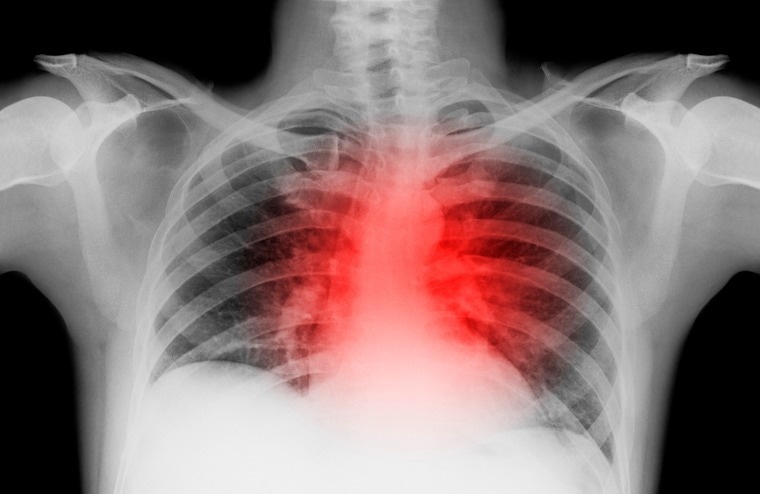

In heart failure, the organ loses the ability to pump adequate blood for the body's needs. This can lead to fatigue, wheezing, weakness, swollen legs and feet and, ultimately, death. Image Credit: UVA Health